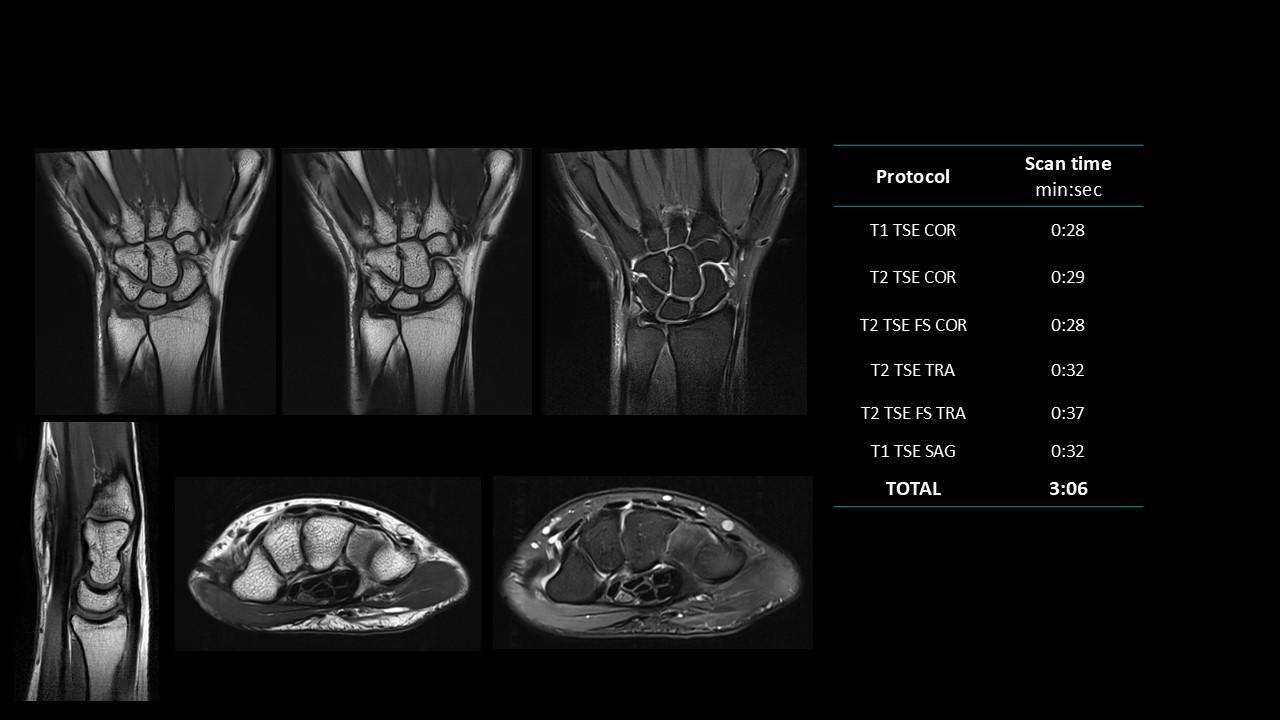

The Deep Resolve protocols are a set of advanced 3T MR imaging protocols designed to achieve high-quality diagnostic imaging with significantly reduced acquisition times.

Enabled by Deep Resolve, the AI-powered image reconstruction technology, these protocols deliver high-quality scans in approximately three minutes across a wide range of anatomical regions.

Developed and meticulously evaluated by Dr. Seong-ho Lee of Leaders Radiology Hospital in Seoul, Korea, the protocols integrate deep learning technology to enhance imaging efficiency while maintaining diagnostic detail.

By reducing scan duration, they improve workflow efficiency and patient experience without compromising image quality.